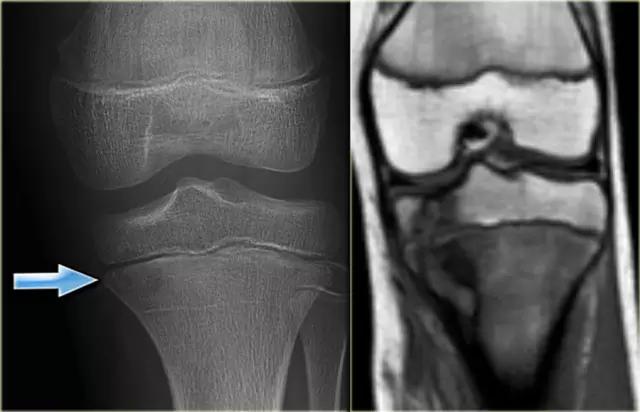

这是亚急性形式的骨髓炎。可以看到在近侧胫骨的骨骺板的两侧的偏心不明确的病变。这是骨髓炎的高度暗示。其他损伤一般不穿过生长板。在右冠状T1加权磁共振成像显示一个明确的骨骺贯通病变。有反应性硬化的暗周边区,并与在干骺端低信号强度广泛水肿。